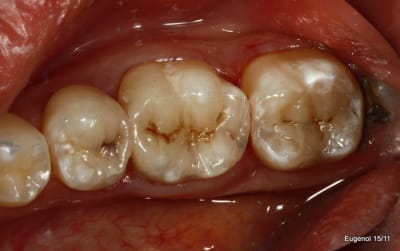

la radio et la photo a 1 mois

Faut avouer qu'ici l'indication du composite sur la 6 est quand même un peu "couillu", en distal par contre il reste une radio clarté: carie résiduelle ou épaisseur de colle importante, en tous cas ça peut fragiliser la suprastucture.